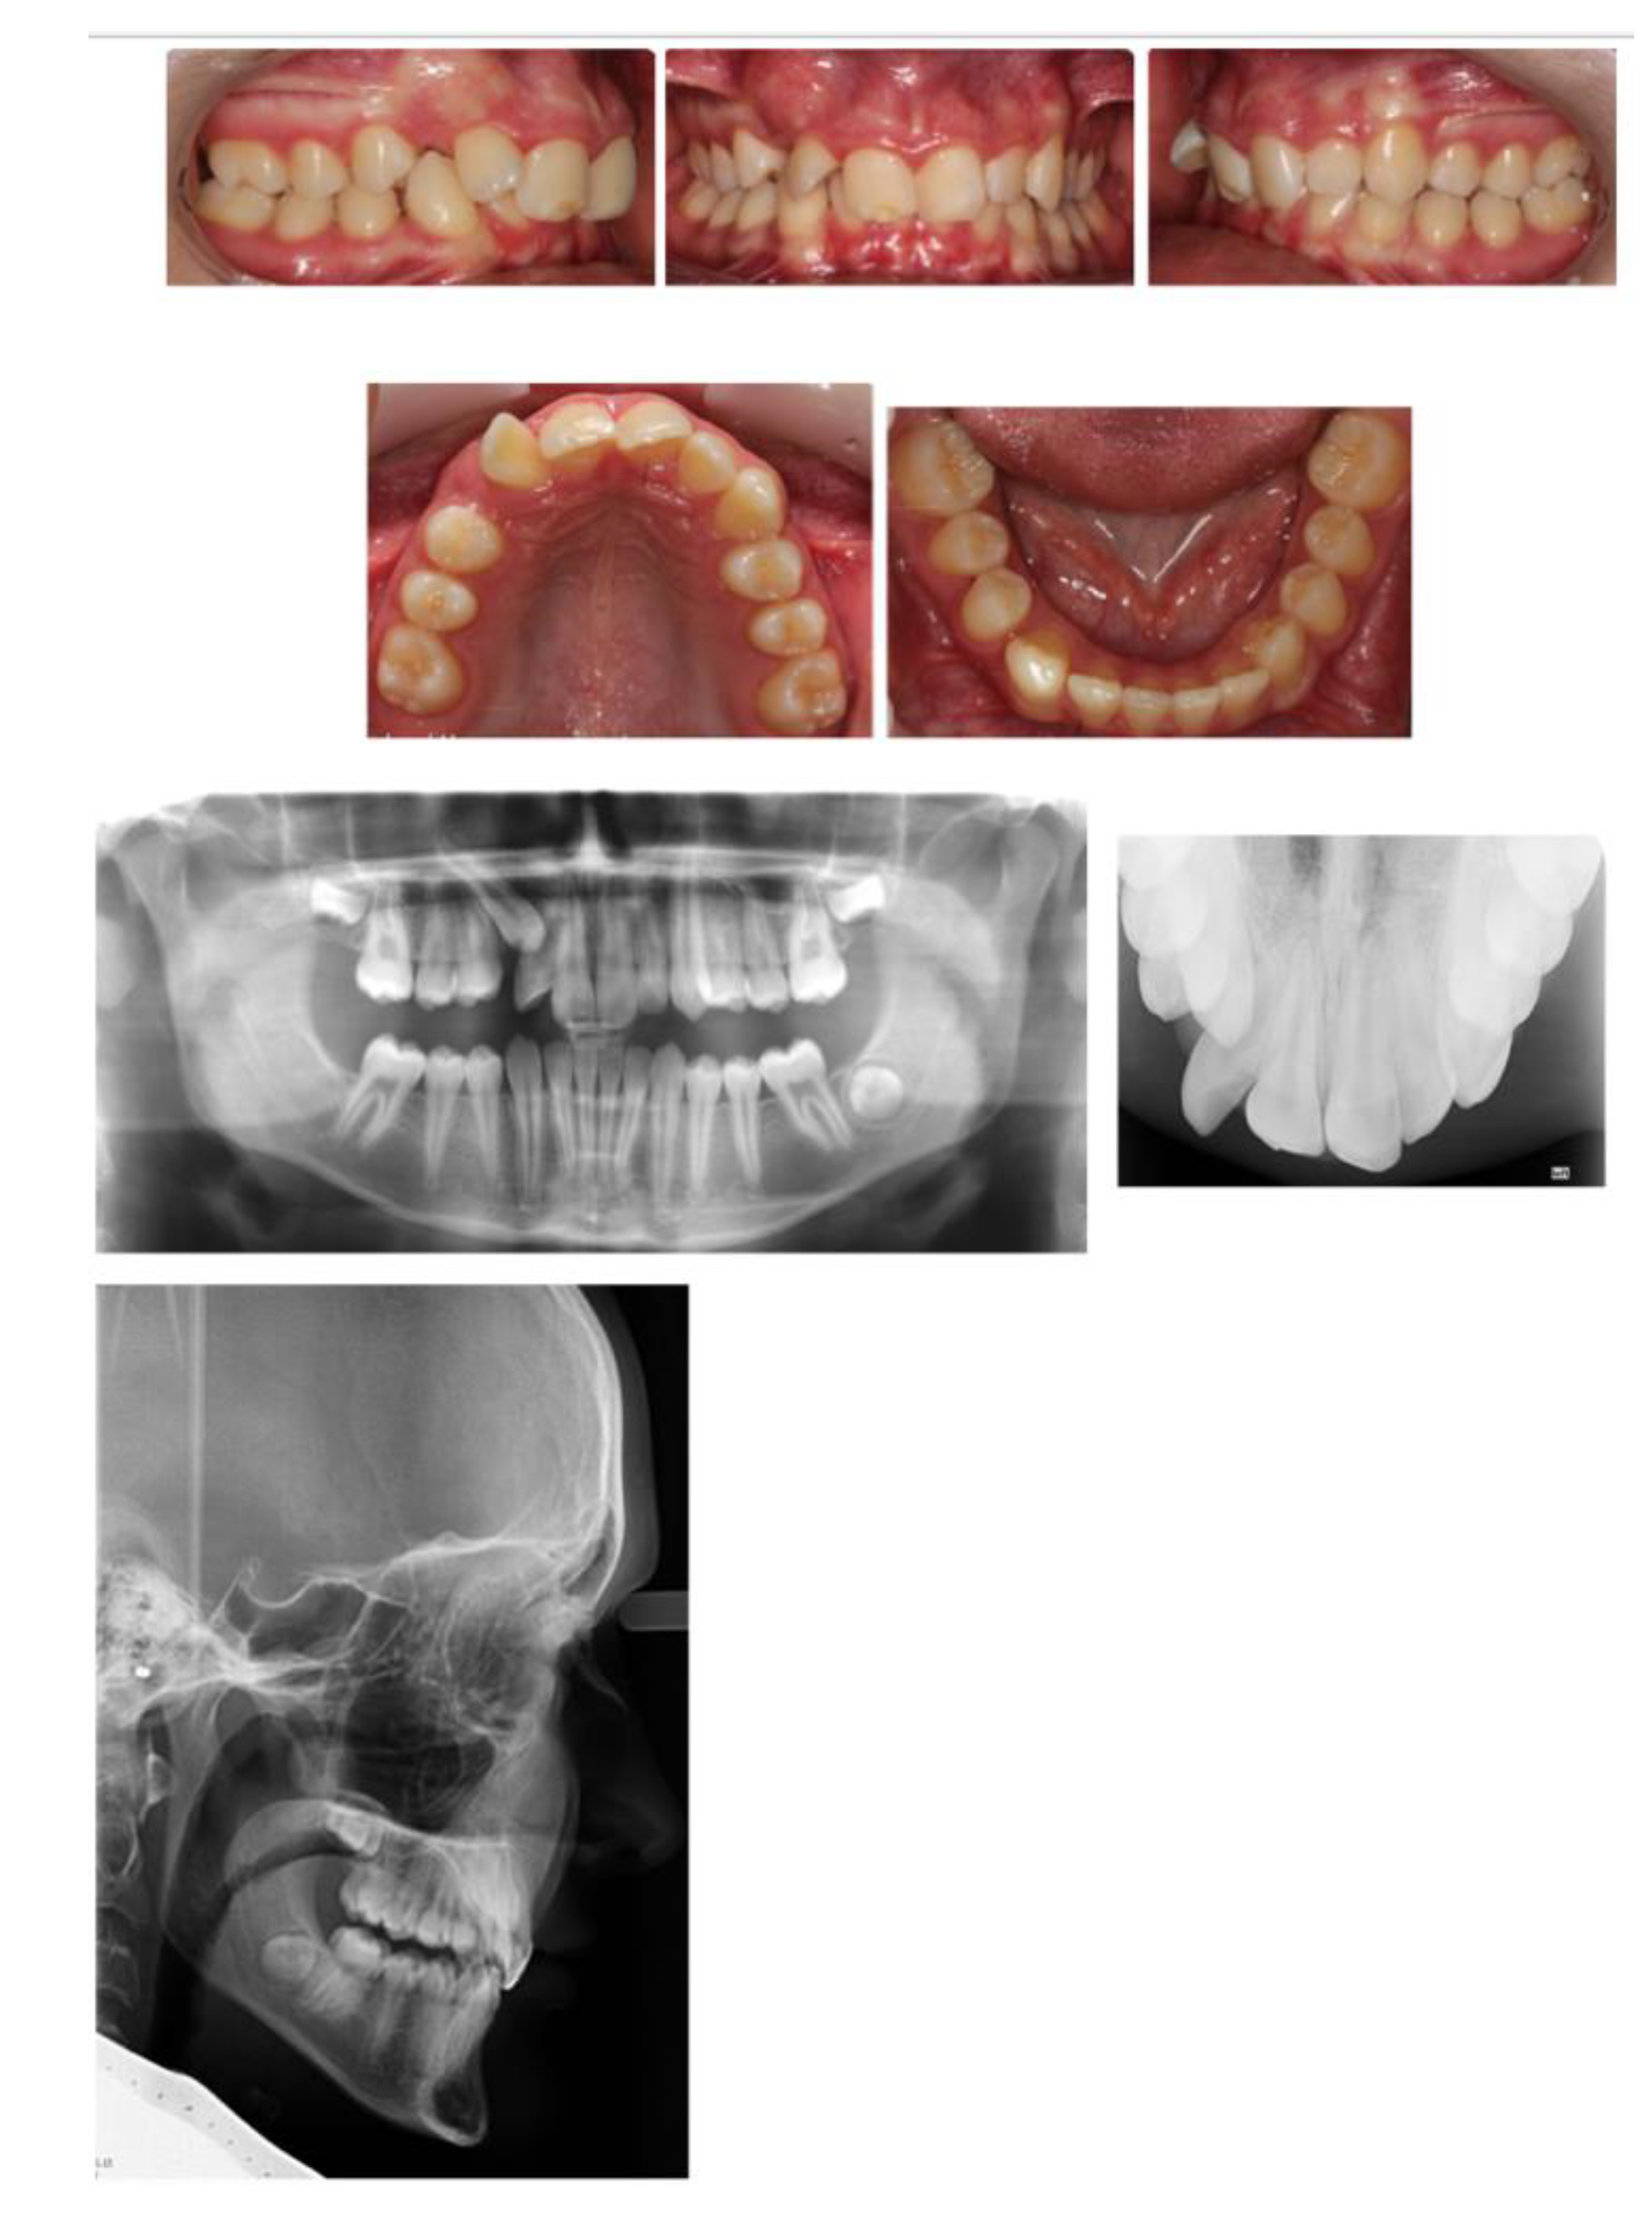

2.2. Case 2—Timely Extraction of FPMs

Discussion

- ▪

- Round tipping of upper and lower second permanent molars;

- Distal tipping of lower second premolars;

- Spacing in the lower arch;

- Excessive retroclination of the lower labial segment that worsened an inherent deepbite.